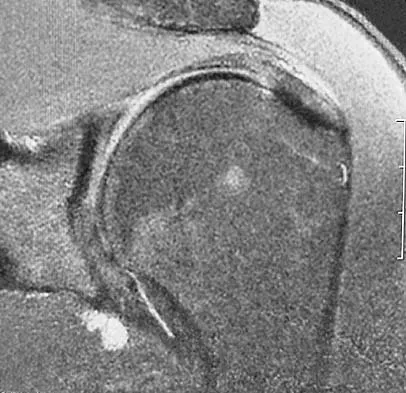

A 40-year-old man reports an enlarging soft-tissue mass in his right shoulder. Based on the MRI scan and biopsy specimens shown in Figures 40a through 40c, what is the most likely diagnosis?

Nodular fasciitis is a pseudosarcomatous, self-limiting reactive process composed of fibroblasts and myofibroblasts. Most patients give a history of a rapidly growing mass that has been present for only a few weeks. Many have pain associated with the mass and can recall a specific traumatic event predating the presence of the lesion. It can occur at any age but is most commonly seen in adults who are 20 to 40 years of age. Histologically, the lesion is composed of predominantly plump, immature-appearing fibroblasts that bear a close resemblance to the fibroblasts found in granulation tissue. Characteristically, the fibroblasts are arranged in short, irregular bundles and fascicles and are adjacent to collagen and reticulin. The lesions can appear to be more myxoid or more fibrotic in nature and this correlates to the duration of symptoms. The lesions with a short duration of symptoms have a more myxoid appearance in contrast to those of longer duration characterized by hyaline fibrosis. Weiss SW, Goldblum JR, Enzinger FM: Enzinger and Weiss's Soft Tissue Tumors, ed 4. Philadelphia, PA, Elsevier, 2001, pp 250-266.